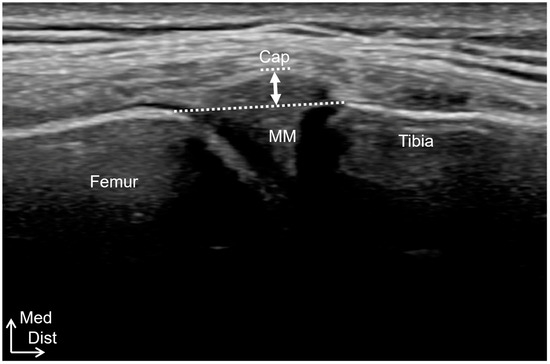

Relationship Between the Sagittal and Coronary Alignment of the Tibiofemoral Joint and the Medial Meniscus Extrusion in Knee Osteoarthritis

Background/Objectives: This study aims to clarify the reproducibility, validity, and accuracy of tibial external-rotation alignment evaluation using ultrasound imaging and to investigate the relationship between medial meniscus extrusion (MME) and tibiofemoral alignment in both the sagittal and coronal planes in knee osteoarthritis [...] Read more.

Background/Objectives: This study aims to clarify the reproducibility, validity, and accuracy of tibial external-rotation alignment evaluation using ultrasound imaging and to investigate the relationship between medial meniscus extrusion (MME) and tibiofemoral alignment in both the sagittal and coronal planes in knee osteoarthritis (OA). Methods: Study 1 included 10 healthy participants. The tibial external-rotation angle was calculated using MRI. In the ultrasound imaging evaluation, the differences in the distance from the most posterior points of the tibial and femoral condyles to the skin were calculated as the medial and lateral condyle gaps, respectively. The mediolateral (ML) gap was calculated by subtracting the lateral condyle gap from the medial condyle gap. Study 2 included 63 patients with unilateral OA and 16 healthy controls. MME was compared according to the severity of OA, the degree of tibial rotation, and the presence or absence of a tibial posterior shift. Results: Ultrasound imaging examinations showed high intra- and inter-rater reliabilities (0.786–0.979). The ML gap significantly affected the tibial external-rotation angle, determined using MRI. The ML gap of ultrasound imaging was significantly correlated with the ML gap of MRI. MME was significantly higher in the Early OA group than in the Control group. There was no significant difference in MME based on the tibial rotation degree. The group with a tibial posterior shift exhibited significantly more MME than that without a posterior shift. Conclusions: Ultrasound imaging is useful for evaluating knee alignment. MME was found to be associated with the tibial posterior shift. Full article